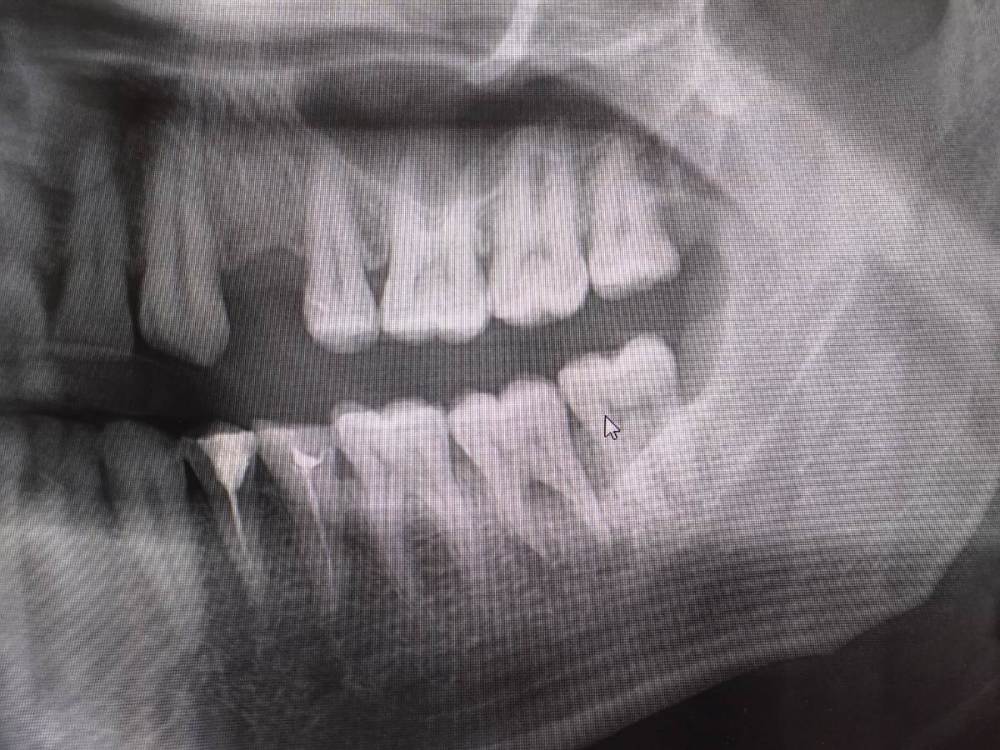

Mihail64 Опубликовано 25 декабря, 2022 Поделиться Опубликовано 25 декабря, 2022 Столкнулся с тем, что 37 зуб плохо сидит в десне (неплотное прилегание, постоянное пощипывание). Ранее при жевании были дискомфорт и несильные болевые ощущения, со временем усилились. Теперь под этим зубом на десне появился постоянно восстанавливающийся гнойник, который я удаляю и полощу хлоргексидином. Был проведен ренген, показавший, что в основаниях двух передних корней зубов были выявлены зоны воспаления. Посоветовали удалить корни и запломбировать, при этом гарантии того, что процесс не возобновится не дают, ссылаясь на переход в хроническое течение (болит более месяца). Как я понимаю сам зуб при этом цел (за ним растет еще зуб мудрости), но есть каналы по которым поступает инфекция. Прошу пояснить, правильно ли назначено лечение, можно ли оставить зуб и при этом избежать повторных абсцессов. Или лучше раз он не держится, и под ним происходит воспалительный процесс, вырвать его. Ссылка на комментарий

Mihail64 Опубликовано 26 декабря, 2022 Автор Поделиться Опубликовано 26 декабря, 2022 (изменено) Похоже перспективы не очень. Поставили также такой диагноз. Под зубом нагноение хронического характера, которое разъело костные ткани корней зуба. Сейчас образовался флюс щеки. Зуб подлежит удалению. Подскажите, ситуация именно такова? Изменено 26 декабря, 2022 пользователем Mihail64 Ссылка на комментарий

Женька Опубликовано 27 декабря, 2022 Поделиться Опубликовано 27 декабря, 2022 Возможно коллеги подскажут, что-то более конкретное. Я лично не вижу показаний к удалению по данному снимку и фото полости рта. КЛКТ возможно показало бы какие-то новые данные. По факту я вижу, что в зубе не было эндодонтии, а значит и прогнозы на излечение так называемой "кисты" очень хорошие. Просто нужен доктор, который возьмётся за лечение Как сказал выше Иван, не приговор. 1 Ссылка на комментарий

DoctorT Опубликовано 27 декабря, 2022 Поделиться Опубликовано 27 декабря, 2022 Нужно исключить трещину в зубе, если ее нет, то обычное лечение корневых каналов. P/S/ снимок конечно, как говорили коллеги КЛКТ. 1 Ссылка на комментарий